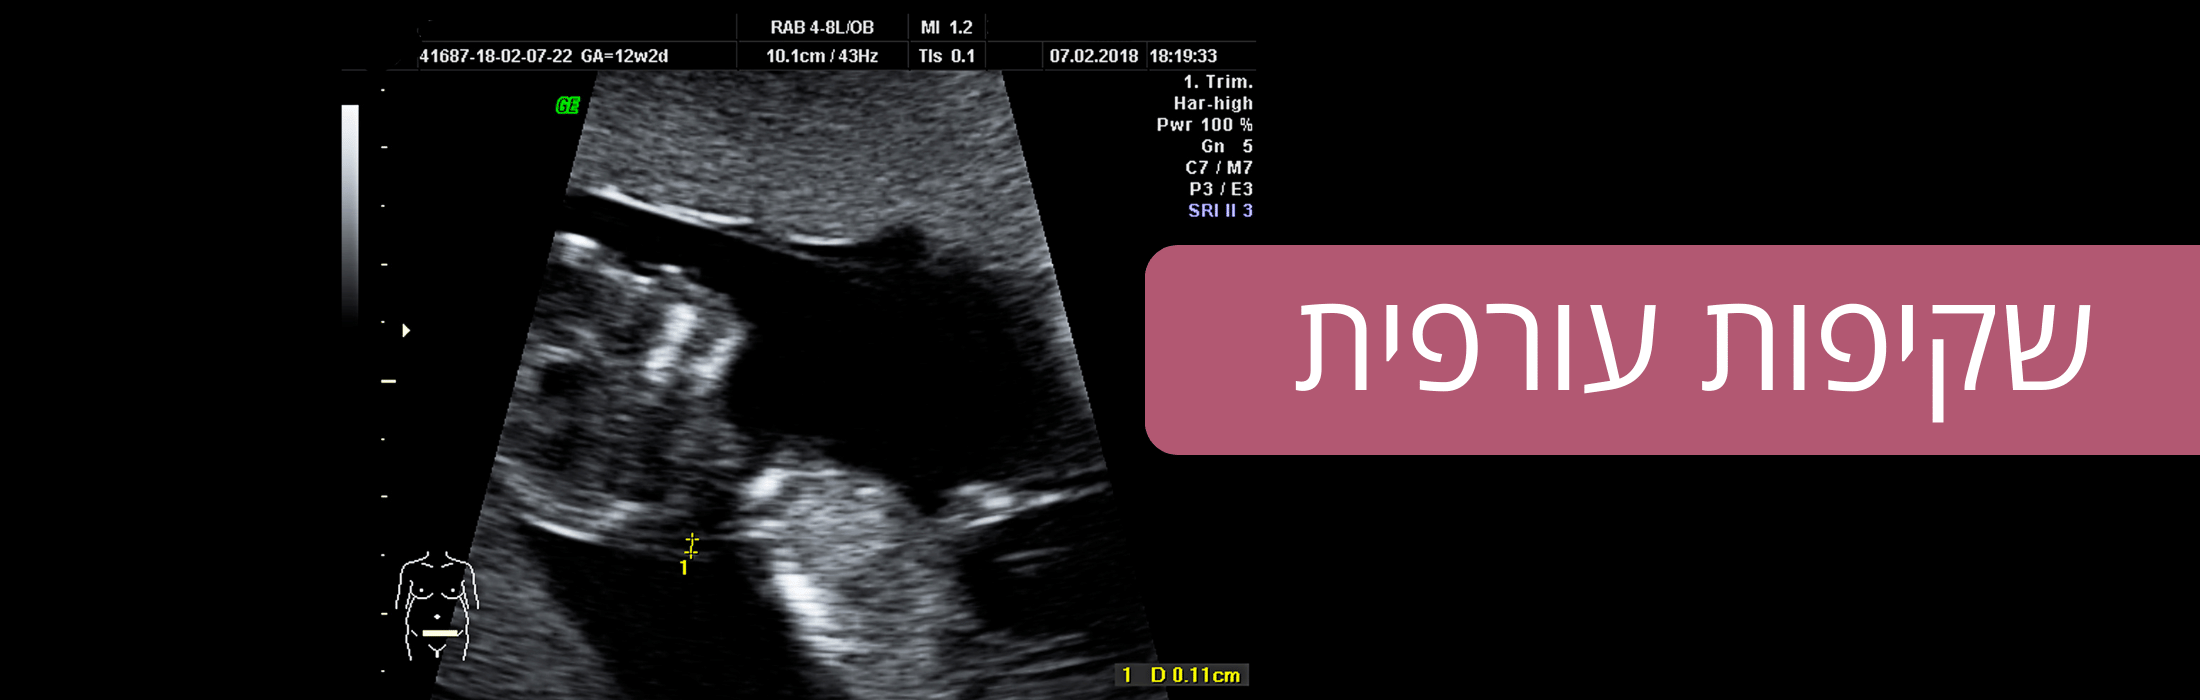

פרופ’ אייל ענתבי הינו גניקולוג בעל שם, ומומחה מוביל בכל הנושאים הקשורים לאולטרסאונד במיילדות וגינקולוגיה ולהריון בר סיכון. הוא מבצע את מגוון בדיקות האולטרסאונד בהריון כולל בדיקת שקיפות עורפית, סקירת מערכות מוקדמת מורחבת, סקירת מערכות מאוחרת מורחבת, בדיקות מכוונות ובדיקות דופלר בהריון. זאת כחלק מהמעקב המיילדותי. בדיקות האולטרסאונד מתבצעות במכשיר חדיש המאפשר גם ביצוע בדיקות תלת וארבע-מימדיות.

בתחום ההריון פרופ’ ענתבי ייעץ לך ויענה על מגוון השאלות הקשורות בהריון תקין ובהריון בר סיכון. פרופ’ ענתבי מבצע גם בדיקות מי שפיר.